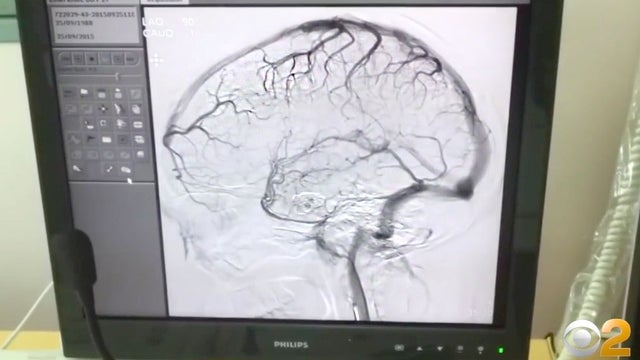

What started as a sinus infection left a Long Island teenager fighting for his life, requiring emergency brain surgery.